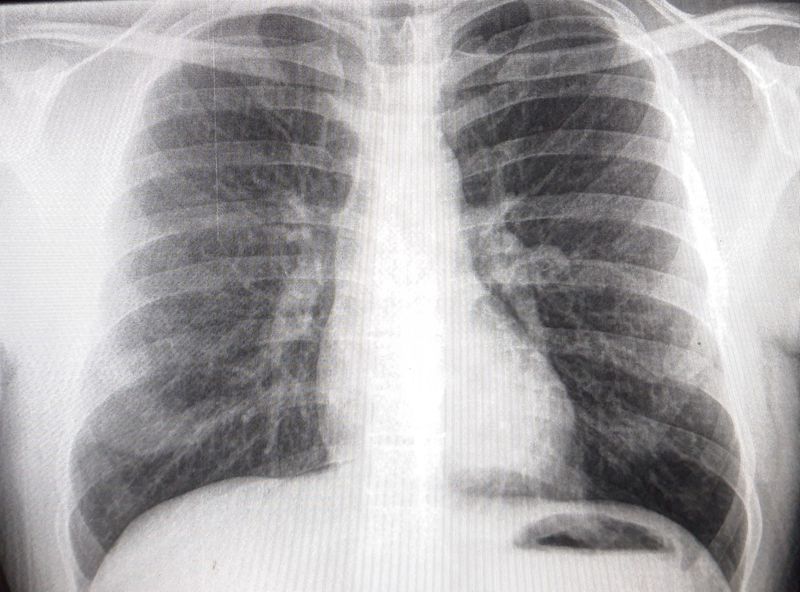

Your diagnosis ??

Chest X-ray

Left lower zone looks darker? Is that a gastric bubble on the left or pneumperitoneum from maybe a perforated peptic ulcer?

That's a gastric bubble. In pneumoperitoneum you can see liver contour on the right.

Is it right pulmonary artery htn

Atelectasis right lower lobe? 🤔

Normal x ray

Pulmonary HTN

Bronchopneumonia

Pneumonia